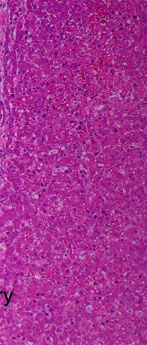

In the large portal area, collagen fibres are separated by oedema fluid. The oedema is also recognisable by the distension of the portal lymphatics.